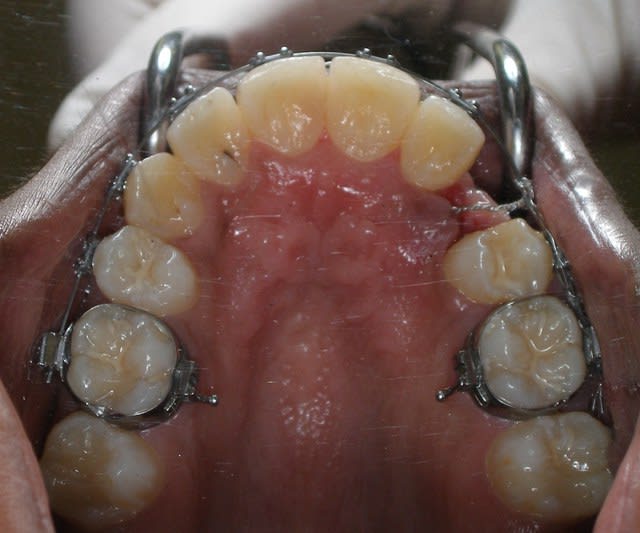

Pour ce cas collage de l'arcade 15 jours avant

sur la photo 2 on distingue les 2 germes l'un au dessus de l'autre (eh non pxav je n'y arrive tjrs pas pour les photos)

trajet , "excision" sinon cela saigne un peu trop, dégagement de la couronne a minima,collage pose de la chainette en traction, régularisation des cretes, sutures

30 minutes entre l'entrée et la sortie de la patiente

dans 8 jours contrôle et pose d'un mainteneur d'espace